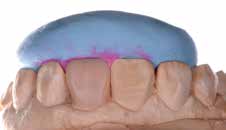

1 2

Fig. 1 et 2 : Situation initiale.

4 5

Fig. 4 et 5 : Choix des masses grâce à la technique des boutons de composite sans et avec filtres polarisants.